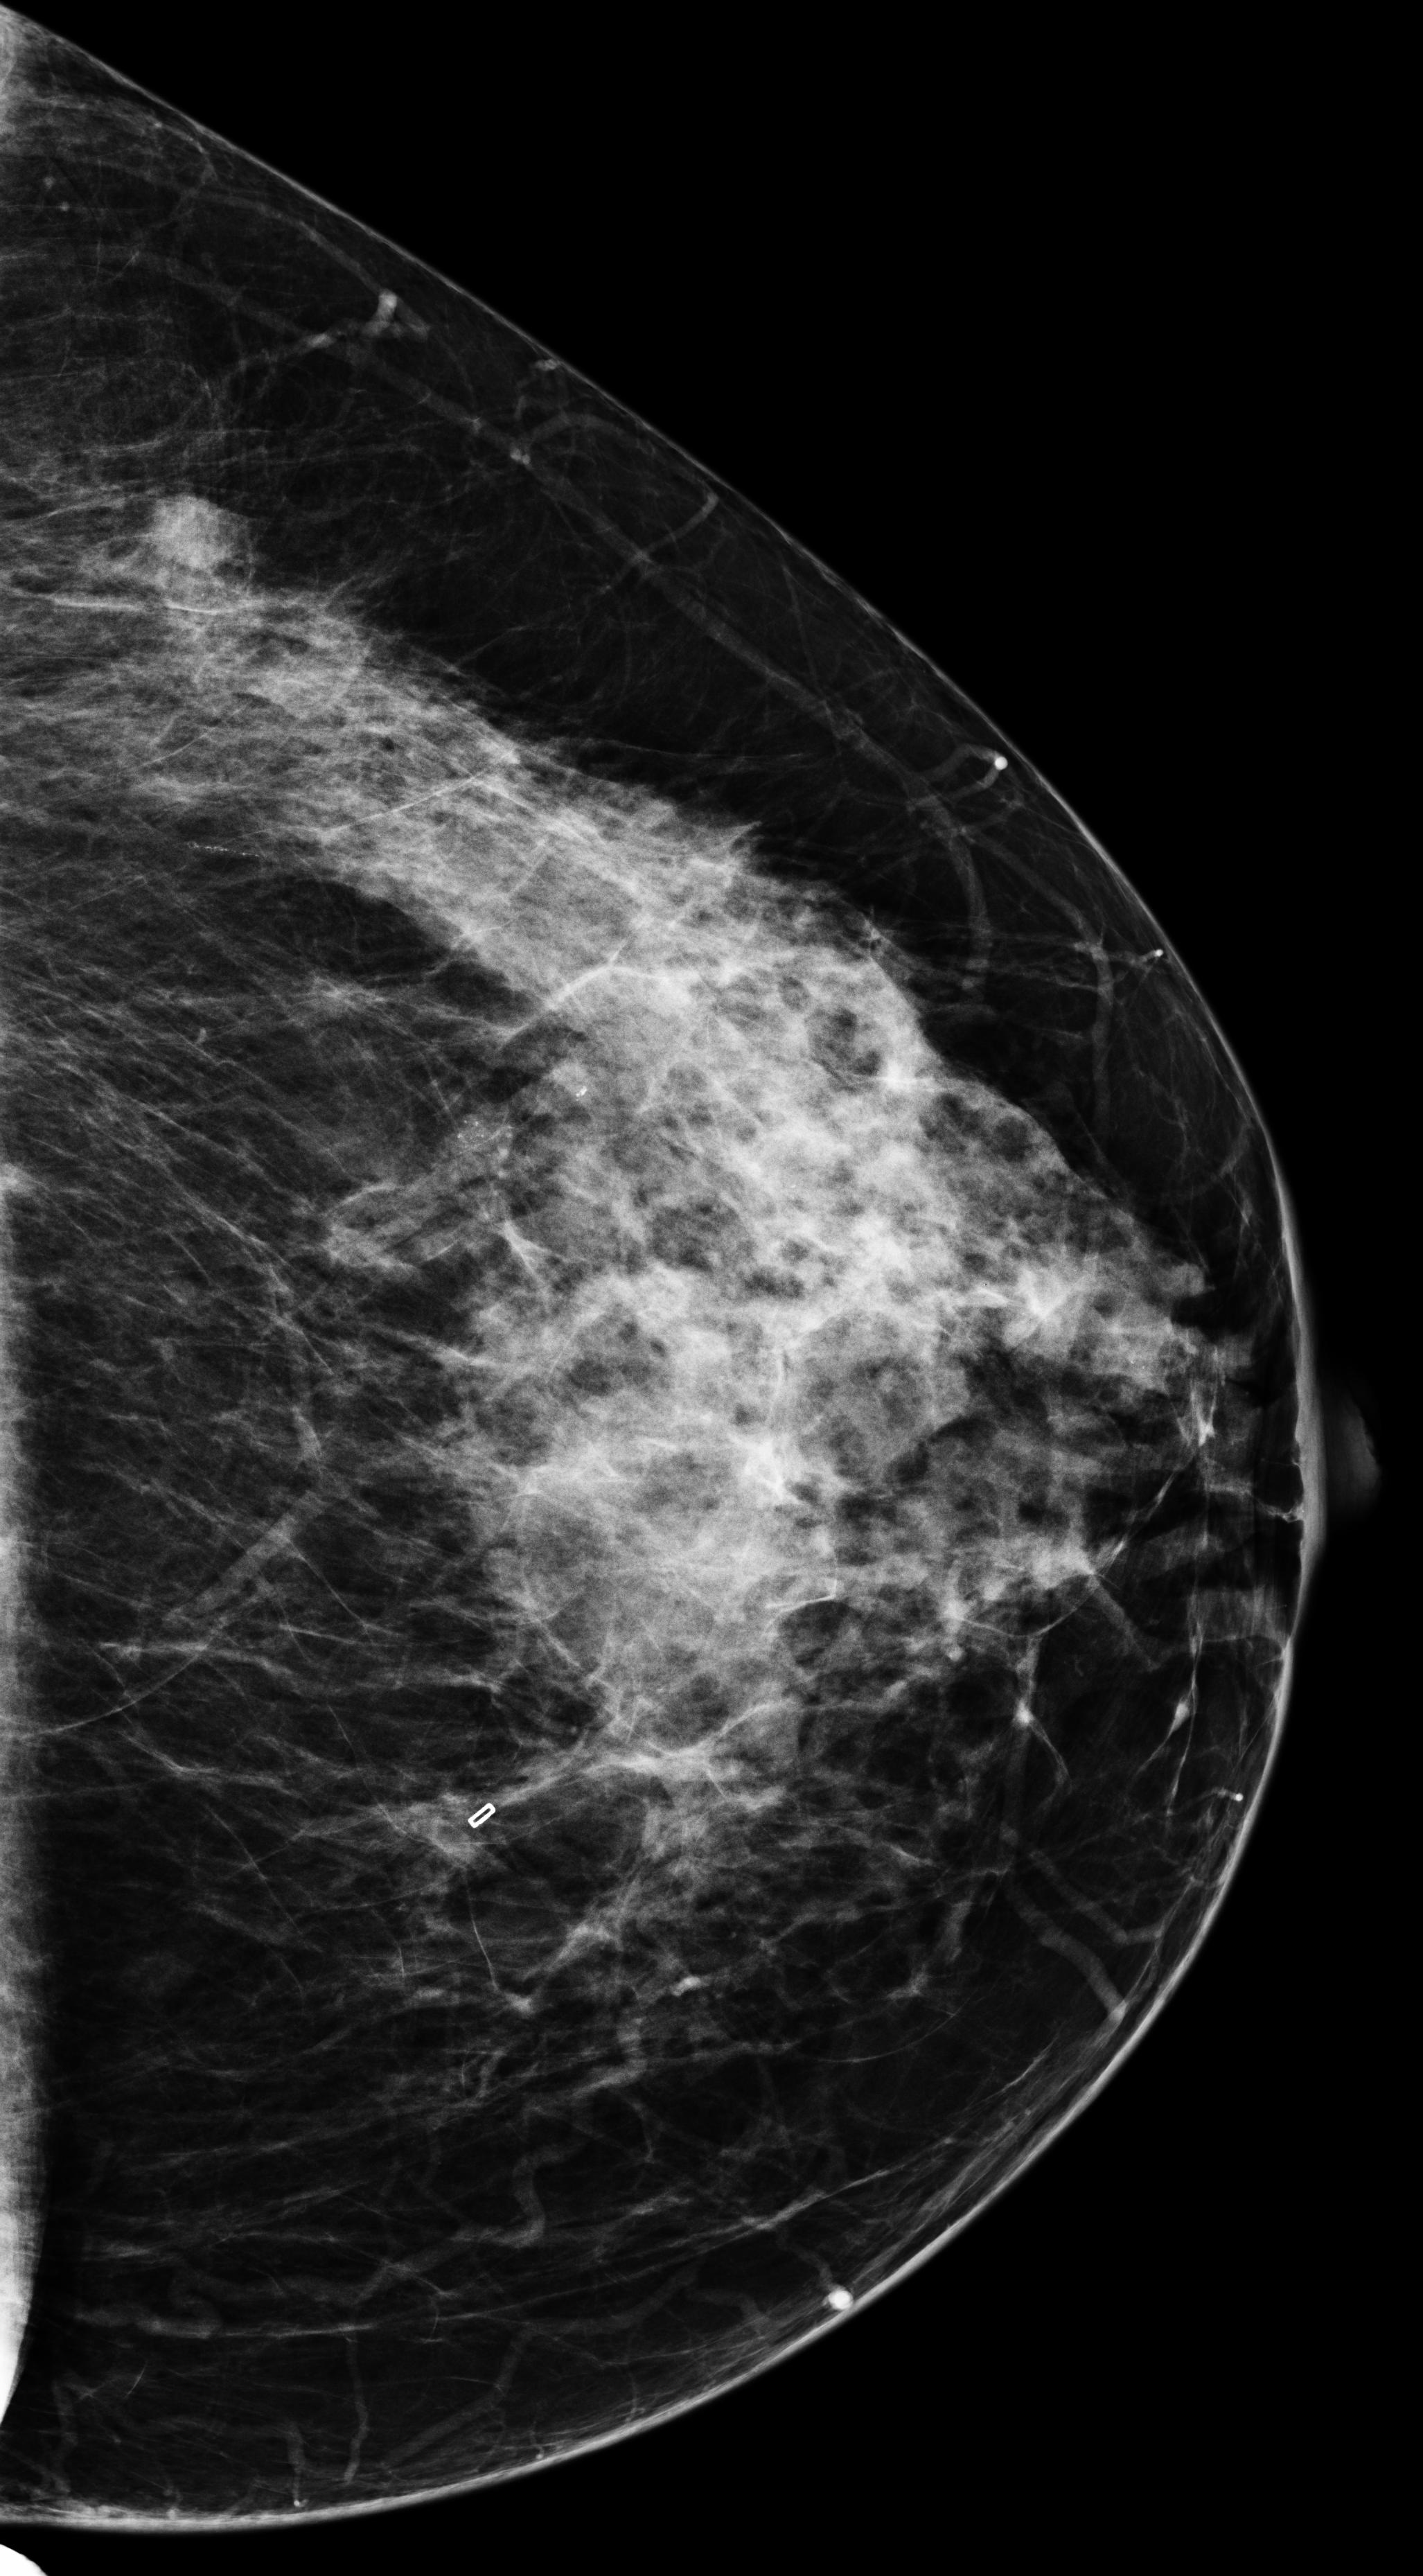

[\capbeside\thisfloatsetupcapbesideposition=left,top,capbesidewidth=6cm]figure[13cm] prior latest highlight prior latest L-CC Refer to caption Refer to caption Refer to caption L-CC Refer to caption Refer to caption L-MLO Refer to caption Refer to caption Refer to caption L-MLO Refer to caption Refer to caption (a) (b)

Figure 3: Test examples where AlignLocalCompare performs better than the single-exam baseline. A breast with a malignant finding shown in (a) (malignant finding is highlighted with red) and one with a benign lesion shown in (b). AlignLocalCompare predicts malignancy with 0.97 probability for (a) and 0.04 for (b), whereas the baseline predicts 0.73 for (a) and 0.24 for (b). There is about a year gap between two exams for both patients.